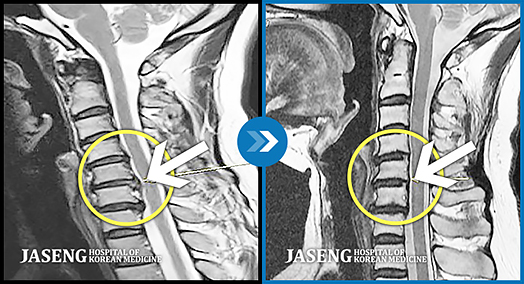

ڻ ѹġḦ ũ ȯ , ܱ ȿ